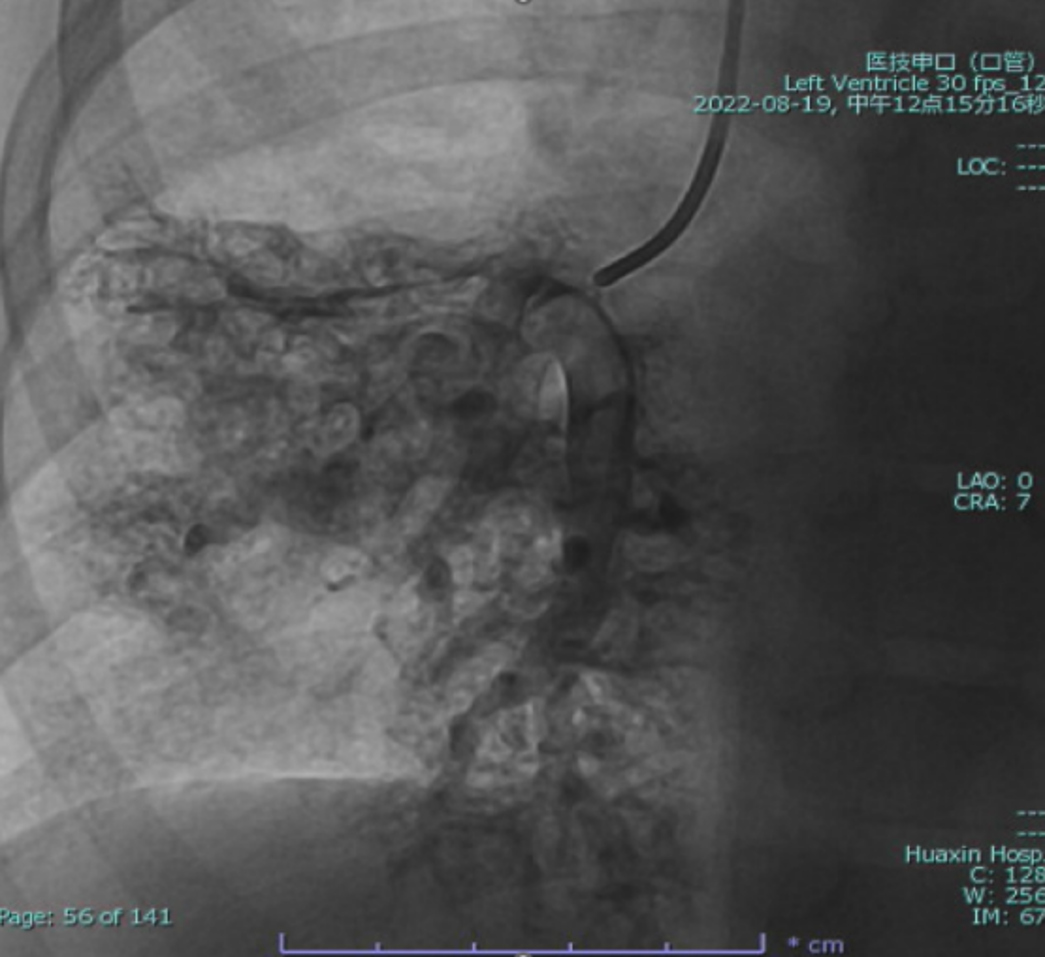

Cardiac catheterization confirmed absence of antegrade pulmonary flow with well-developed bilateral pulmonary arteries. Distal pulmonary arteries and pulmonary venous branches were markedly dilated, some showing a granular or ¡°string-of-beads¡± appearance. Pulmonary circulation time was shortened, indicating significant right-to-left intrapulmonary shunting consistent with diffuse PAVMs. Pulmonary artery pressure was 17/9/13 mmHg.